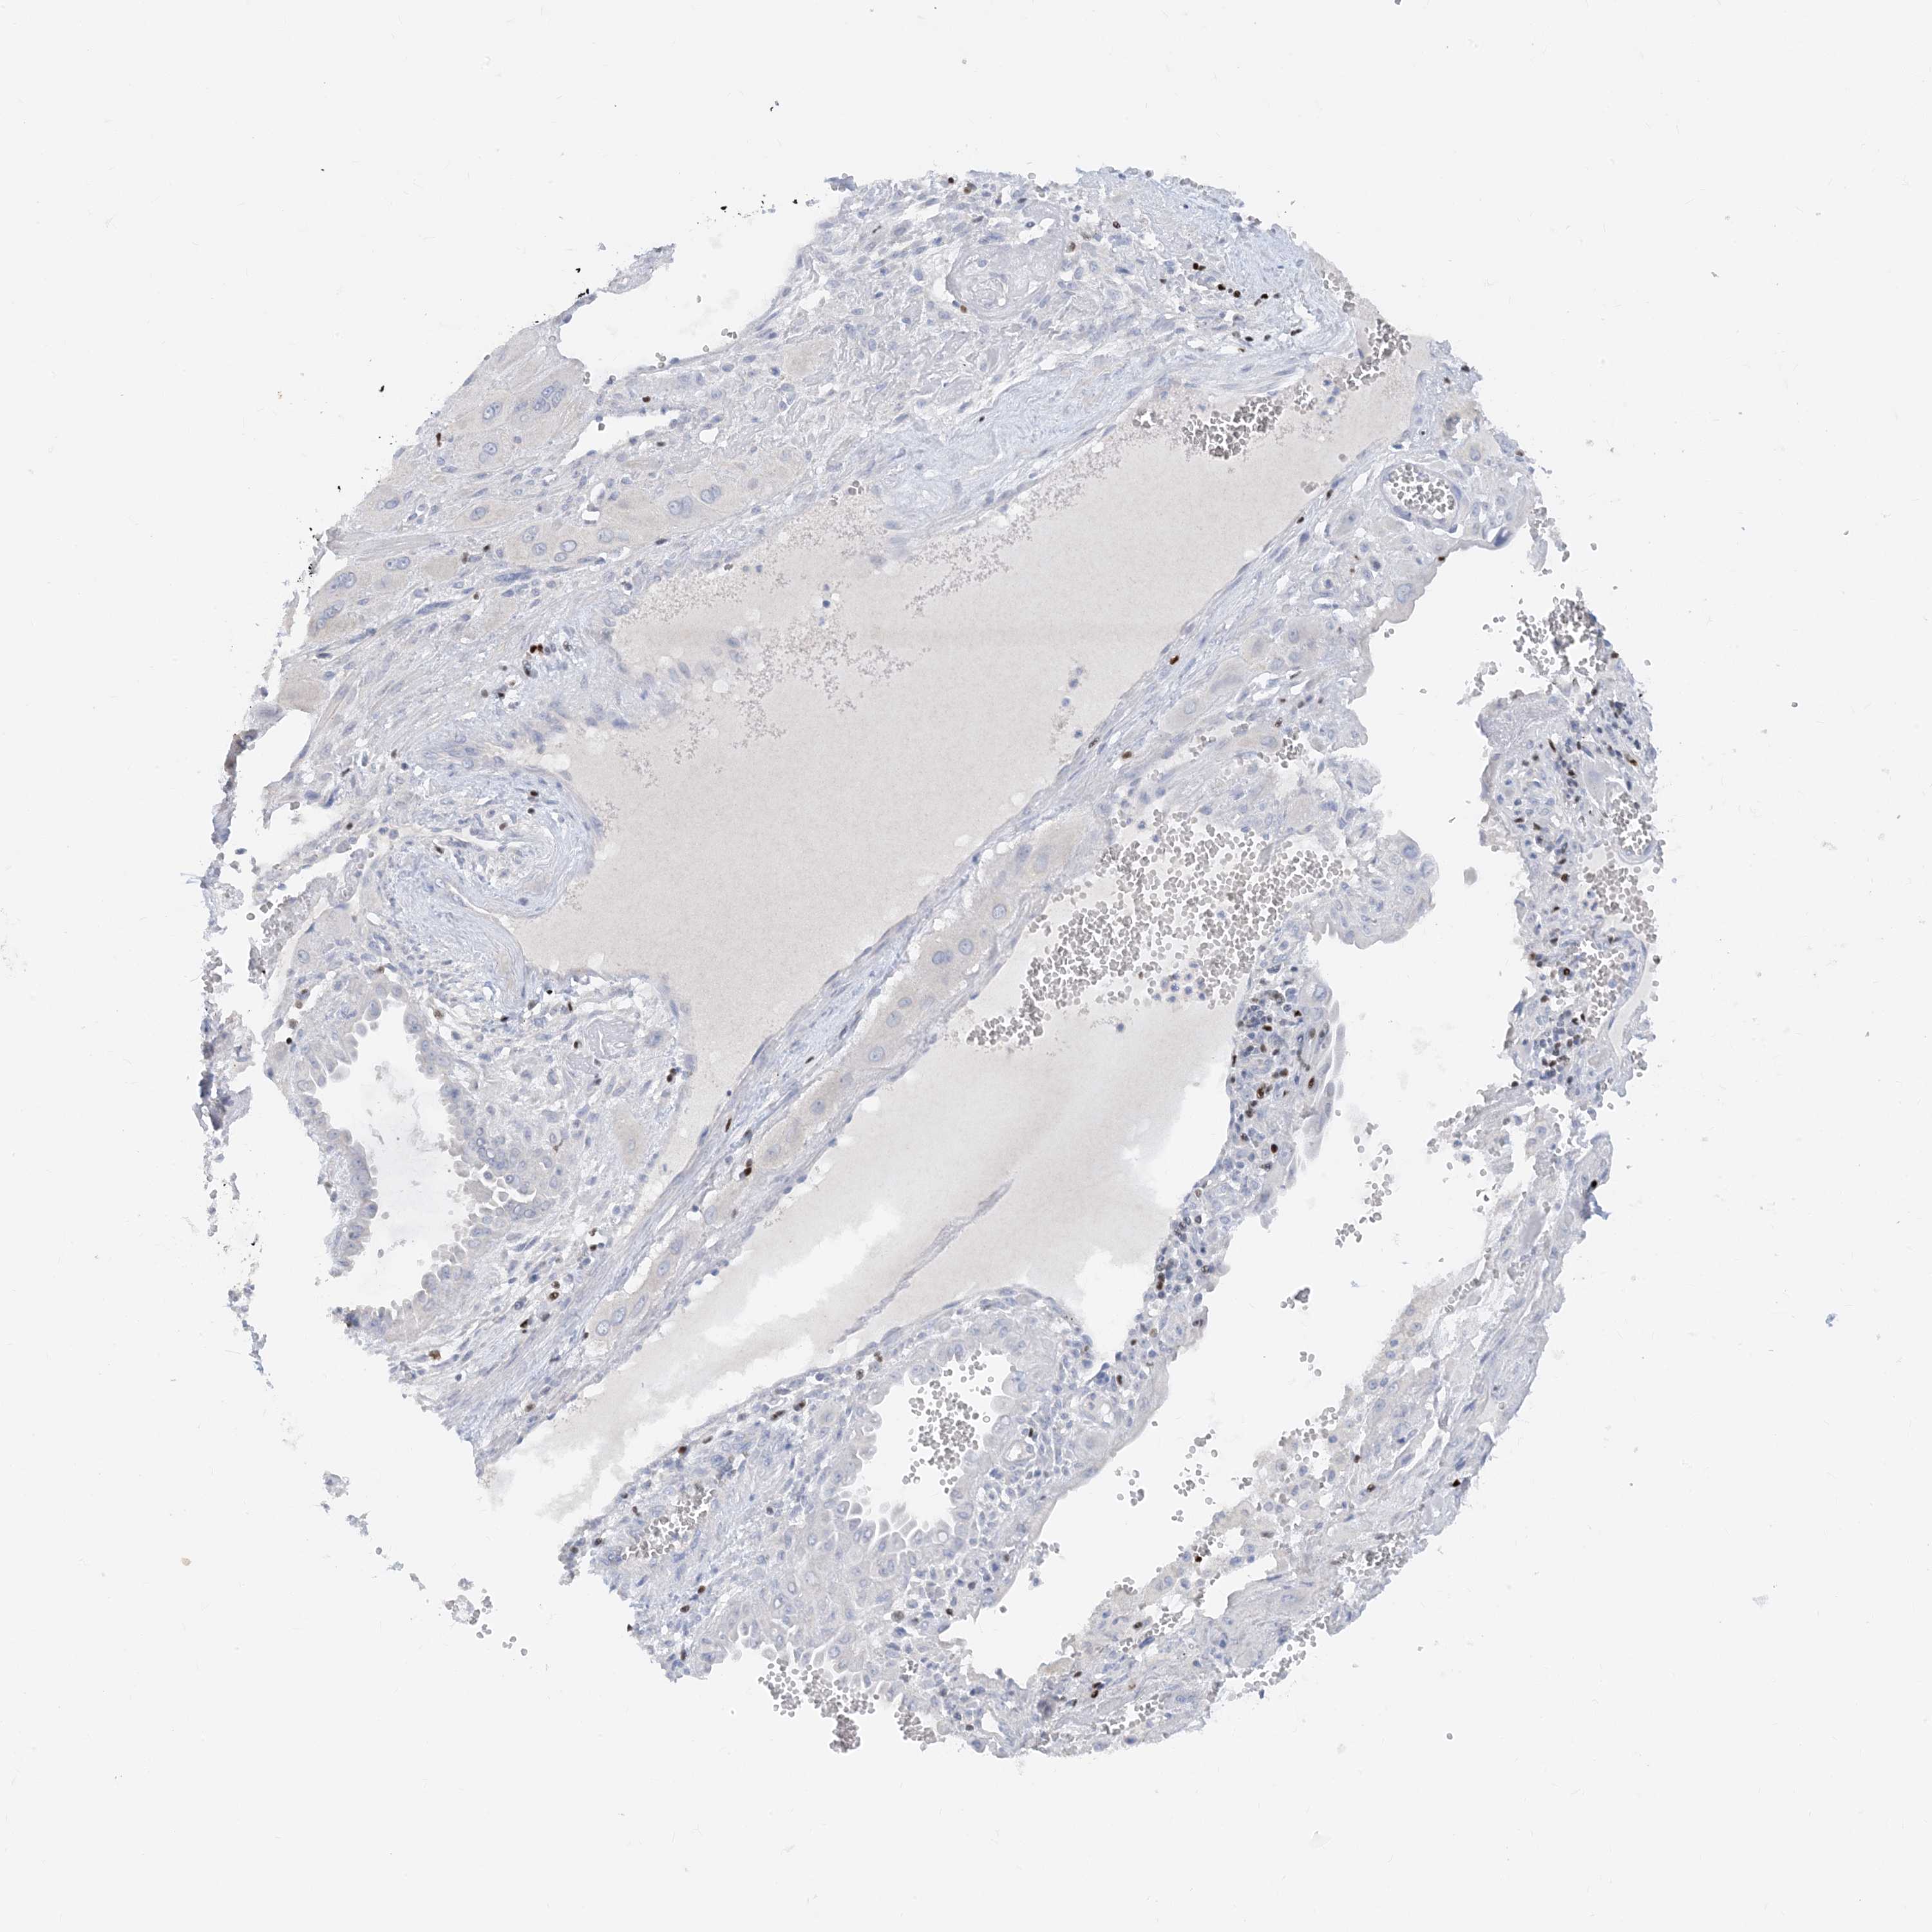

TBX21